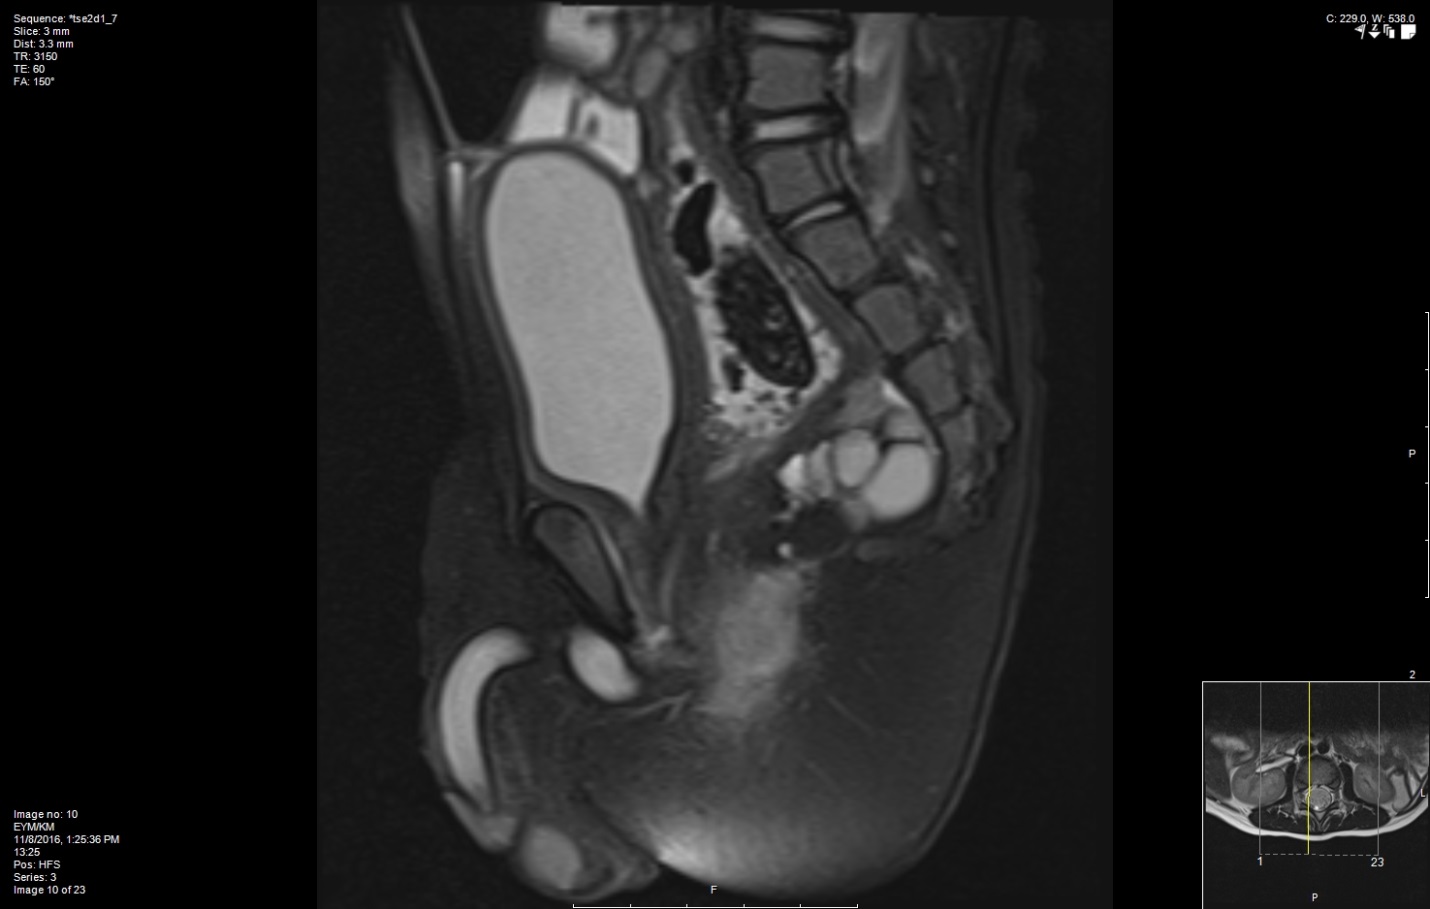

Case Presentation: 21 month old male presents to the hospital for constipation that failed outpatient therapy. Parents describe one hard difficult to pass bowel movement (BM) every other day, without pencil thin stools, blood or mucus. Constipation began at 3 months of age when they introduced formula. He passed meconium within the 24 hours of birth and was growing and developing normally. Parents tried lactose free formula, laxatives and fruit juice with minimal imporvement. He had two prior hospitalizations for constipation requiring manual disimpaction. He was admitted to our facility for further workup. There was no family history of constipation, Cystic Fibrosis, Hirschprung’s Disease or Hypothyroidism. On Physical exam the patient was alert, active and in no acute distress, cardiopulmonary exam was within normal limits, the abdomen was distended but non-tender to palpation, stool burden was palpable and bowel sounds were present. Rectal exam was deferred until the patient was sedated. The next day he was taken to the operating room for a digital disimpaction under anesthesia and was noted to have increased anal tone with a funneled rectum, a rectal manometry confirmed that he had an anal fistula and surgery was consulted. Pelvic Magnetic Resonance Imaging (MRI) was obtained which showed a presacral teratoma (image1), spinal X-ray and MRI where within normal limits. He was diagnosed with Currarrino Syndrome (CS) and corrective surgery was scheduled. To this date he has undergone corrective surgery including resection of presacral mass with diverting colostomy, anorrectoplasty, multiple dilations and colostomy takedown, he continues to require rectal dilations. The presacral mass was determined to be a benign mature teratoma by pathology and a rectal biopsy was negative for Hirschprungs disease.

Discussion: Currarino syndrome is a rare complex syndrome characterized by a sacral bone defect, anorectal malformation, and a presacral tumor. Although complete triad presentation is rare. The most common presenting symptom is constipation but most cases are asymptomatic and diagnosed incidentally. In a multicenter retrospective data collection study they found that almost half of the patients had been diagnosed with CS after 1 year of age and only 23.5% by the first month of life. The diagnostic approach is imaging based and should include radiographs and pelvic and spinal MRI for evaluation of presacral masses and spinal anomalies. In our case the radiographs and spinal MRI did not show skeletal abnormalities but the pelvic MRI did show a presacral mass. Management is surgical and should be tailored to each individual case as in our patient who required a step-wise surgical approach.